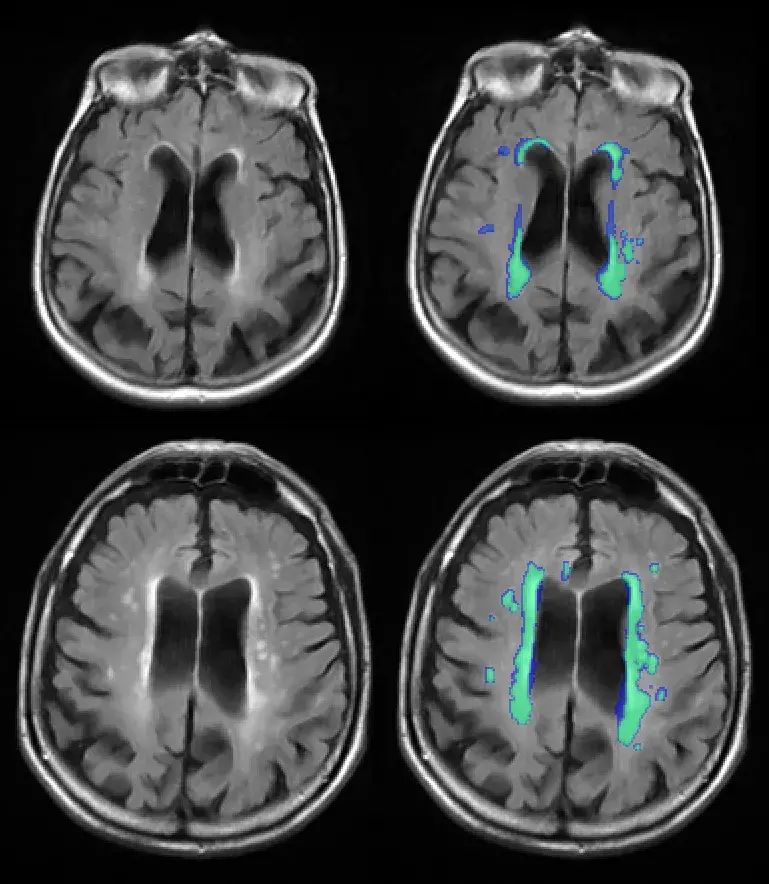

At The Row Fogo Centre for Research into Aging and the Brain, we are dedicated to improving understanding of the brain damage caused by small vessel diseases (SVD) Although SVDs have been recognised to be a main cause of age-related brain diseases such as stroke, dementia and Alzheimer’s disease, there is still very limited understanding of this common disease.We study people to understand how SVD starts and affects them. We use sophisticated medical imaging methods such as magnetic resonance imaging (MRI) to find out about how SVD is affecting the brain and blood vessels. To extract information from the brain MRI, we have developed highly specialised computer methods to analyse the images. The medical analysis tools and image databanks from our studies allow us to improve early detection and diagnosis of SVDs, identify causes and the consequences of SVDs, and to develop methods for prevention and treatment of small vessel diseases (SVDs). Moreover, our research discoveries contribute to advancing understanding other common disorders such as Multiple Sclerosis and Motor Neuron Disease.The Row Fogo Centre for Research into Aging and the Brain aims to promote early career researchers by supporting the development of their research skills in the field of cerebral SVD. With a specific focus on the young researchers, The Row Fogo Centre holds workshops, provides lectures in image analysis, and advice and training. The Row Fogo Centre sponsors events at the University of Edinburgh to exchange knowledge and promote the scientific work of all who are interested in SVDs. Methods developed at the Row Fogo Centre are incorporated into the Imaging MSc, other training programmes and short online courses for future generations of medical professionals. Related links Row Fogo Centre Research Projects Ways to fundraise or make a donation to support our research Impact of your donations on our research Image analysis tools (external link) Training programmes and short online courses in medical imaging (external link) This article was published on 2024-08-27